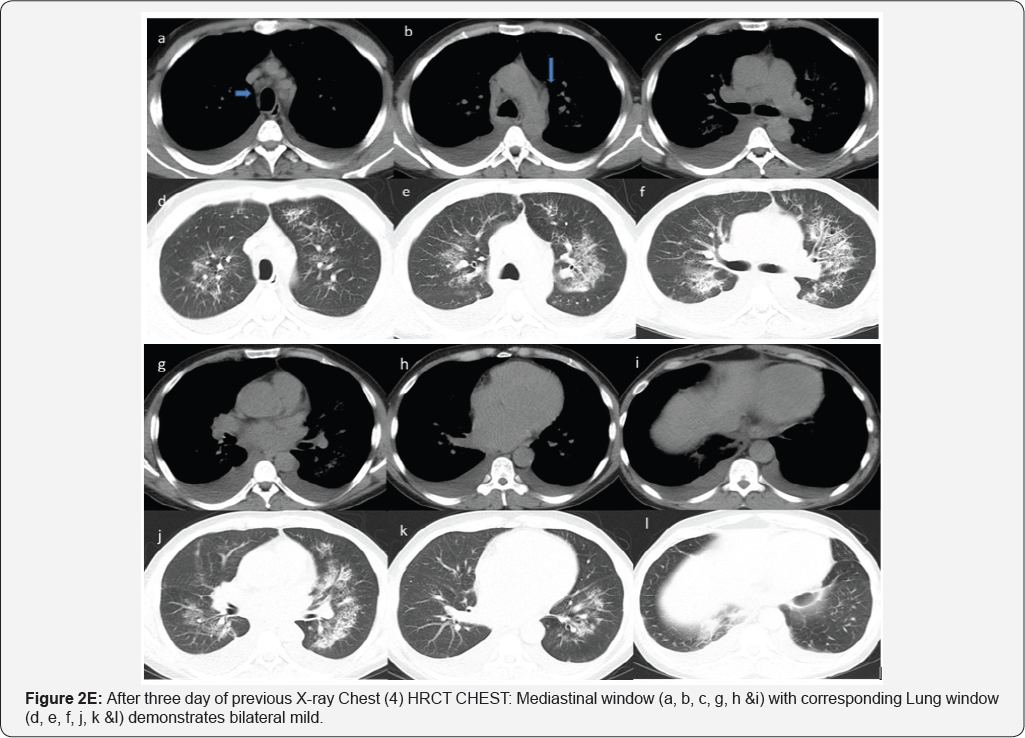

X-Rays and CT during his Hospital stay: (Figure 2A-2E)

Pleural effusion (RT>LT) multiple small mediastinal lymph nodes (arrow in image a & b), likely reactive. Bilateral perihilar airspace diffuse air space opacity and ground-glass attenuation with superimposed interlobular septal thickening and intralobular lines (LT> RT). Common differential of Crazy paving given as well as diagnosis of pulmonary edema (uncommon cause of crazy paving) given in view of history of CHF and improvement by treatment. Superimposed infection is likely in view of high inflammatory markers (Figures 3A & 3B).